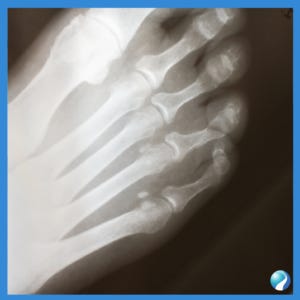

What is a Proximal Phalanx Fracture?

The bones in each toe are known as phalanges (singular: phalanx). When one of these bones is fractured, it’s referred to as a phalanx fracture. Specifically, a proximal phalanx fracture occurs in the phalanx closest to the base of the toe, which can impact mobility, weight-bearing ability, and balance.